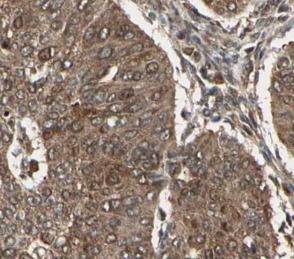

| 验证图片 | Immunohistochemical of paraffin-embedded human pancreas using FNab01611(CEPT1 antibody) at dilution of 1:50 Immunofluorescent analysis of HepG2 cells, using CEPT1 antibody FNab01611 at 1:25 dilution and FITC-goat anti-Rabbit IgG (green). |